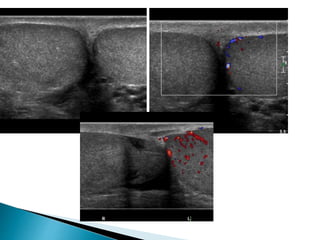

 On ultrasound varicoceles are seen as a

echo-free serpiginous structures measuring

more than 2 mm maximum diameter .

 Visible flow may he seen within larger

varicoceles.

 Their prominence is increased in the

upright position and with the Valsalva

manoeuvre.